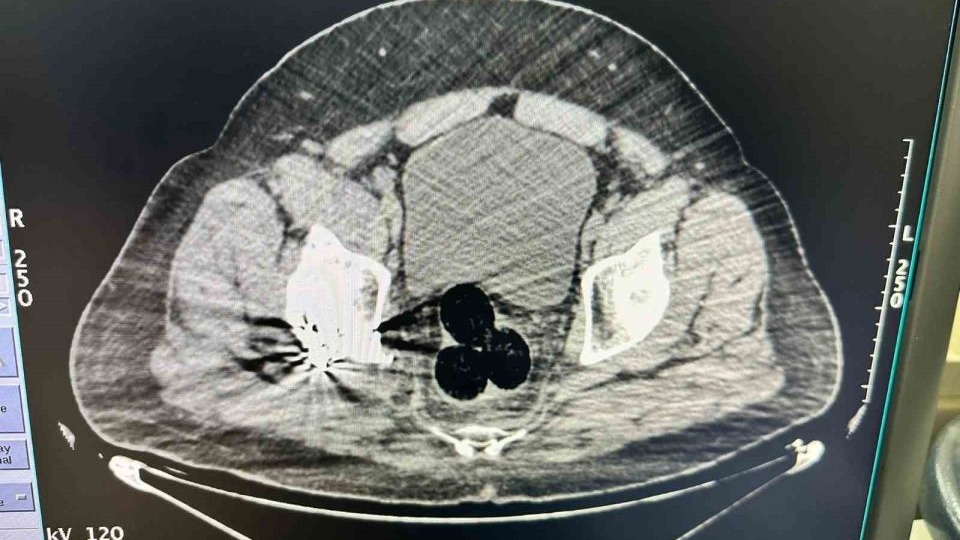

Edinilen bilgiye göre, İl Emniyet Müdürlüğü Narkotik Suçlarla Mücadele Şube Müdürlüğü ekipleri, İran’dan Türkiye’ye yasa dışı yollardan giriş yapan bir kişiyi şüphe üzerine takibe alındı. Gözaltına alınan şahıs hastaneye götürüldü. Hastanede yapılan görüntülemede şüphelinin makat bölgesinde üç parça halinde yabancı cisim tespit edildi. Cerrahi müdahale ile çıkarılan paketlerde toplam 130 gram metamfetamin ele geçirildi, şüpheli gözaltına alındı. Soruşturmayı derinleştiren polis ekipleri, uyuşturucunun kentte dağıtımını yaptığı değerlendirilen iki şüpheliyi daha yakaladı. Bu kişilerin üzerinde ve adreslerinde yapılan aramalarda 47 gram daha metamfetamin ele geçirildi.